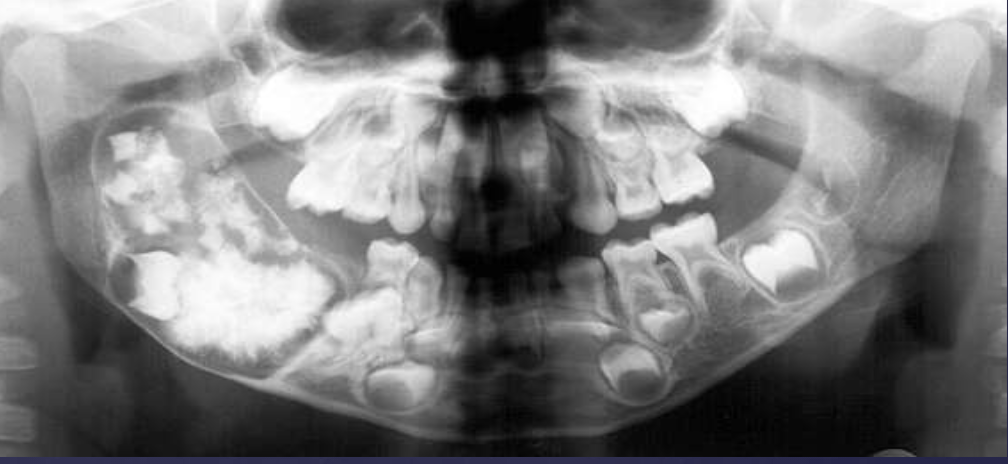

describe what’s occurring in this radiograph

pericoronal/mural; impacted tooth

displacement of #32 + IAN

osseous expansion

thinning of cortices